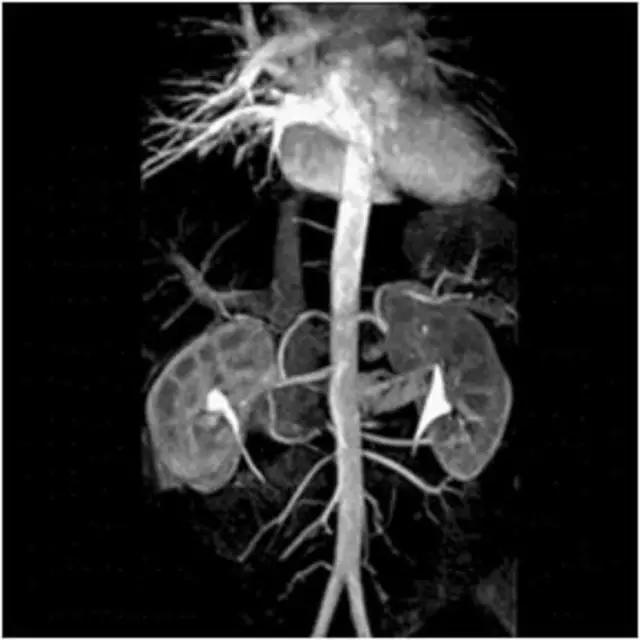

3、心脏大血管